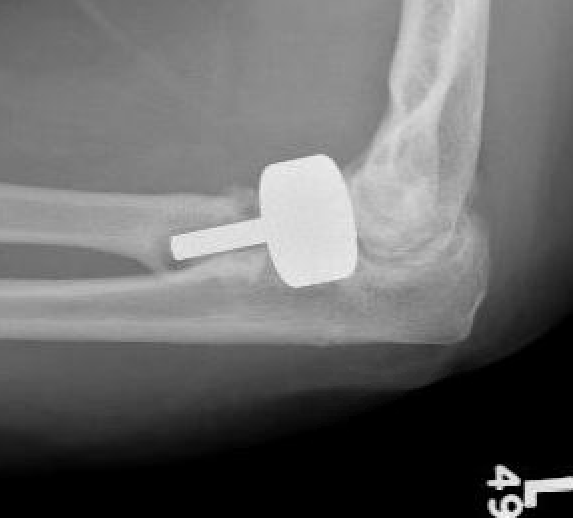

Overstuffing

| Lesser sigmoid notch | Symmetry of ulnohumeral joint |

|---|---|

|

Radial head shoulder articulate with lesser notch

Ensure no gapping of lateral ulnohumeral joint |

![]() |

- cadaveric study

- increased medial ulno-humeral joint line gapping with overlengthening of 6 or 8 mm

- increased lateral ulno-humeral joint line gapping with overlengthening of 2 mm